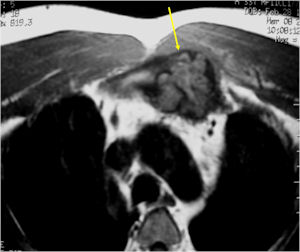

MRI:

- Also useful in determining extent

- There is often extensive edema around the tumor in the surrounding bone and soft tissues that can lead to a misdiagnosis of a malignant tumor.

- Soft Tissue Mass with an Osteoblastoma